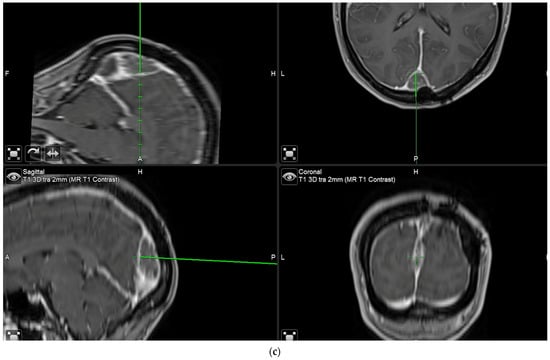

After clearing a field from tumor under white light, with the surgeon no longer being able to identify residual tumor in that field of view, the surgeon has the possibility of switching to blue light to determine whether any pathological tissue can be identified based on fluorescence. If the surgeon finds residual fluorescing tissue after switching to blue light, this area is pointed out using the neuronavigation pointer (and a navigation screenshot is taken). A biopsy is taken from the exact same region after switching back to white light if this can be performed safely. This procedure is also recorded by video from beginning to end. Such interrogations might be performed at multiple stages of surgery, provided a particular area (field of view) has been cleared of tumor according to the impression of the surgeon under white light. The interrogation of an inconspicuous bone flap also constitutes an “end of surgery” scenario if the surgeon wants to rule out any tumor infiltration in the bone. If any fluorescent bone is encountered, then this is biopsied prior to drilling of the bone flap (Figure 3).

“End of surgery” biopsy: After clearing a field from tumor under white light, with the surgeon no longer being able to identify residual tumor in that field of view, the surgeon switches to blue light to determine whether any pathological tissue can be identified based on fluorescence. Any fluorescing tissue is pointed out using the neuronavigation pointer (and a navigation screenshot is taken). A biopsy is then taken collected. This procedure is recorded by video from beginning to end. (a) After dissecting tumor from the brain, the brain is considered free of tumor. (b) Various areas of fluorescence can be observed. The surgeon would then resect the fluorescing tissue shown. (c) Navigation pointer and corresponding screenshot (“F”: footwards; “H”: headward; “A”: anterior; “P”: posterior; “L”: left; “R”: right).